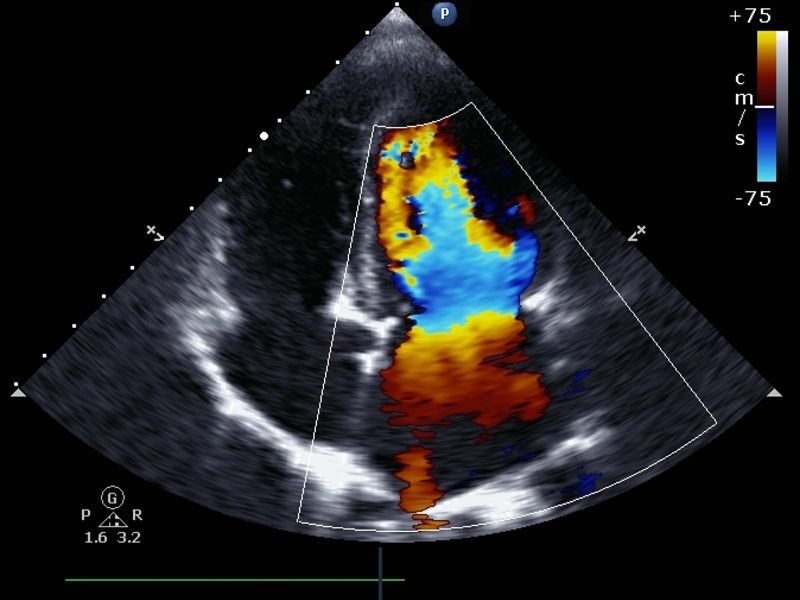

A Clínica Saúde e Vida oferece o ultrassom abdome superior com Doppler em Goiânia, GO. Este exame é indicado para avaliar a saúde dos órgãos abdominais superiores, como fígado, baço, pâncreas e rins, ao mesmo tempo em que verifica o fluxo sanguíneo nas artérias e veias dessa região. Com o uso do Doppler, é possível detectar condições como trombose, obstruções vasculares e problemas circulatórios.

O ultrassom abdome superior com Doppler é um exame que combina duas tecnologias essenciais: a imagem anatômica dos órgãos abdominais superiores e a avaliação do fluxo sanguíneo. O Doppler usa ondas sonoras para analisar o movimento do sangue nas artérias e veias, fornecendo informações detalhadas sobre a saúde vascular da região abdominal superior.

Esse exame é fundamental para pacientes que apresentam sintomas como dor abdominal superior, dificuldade digestiva ou histórico de problemas circulatórios. Ele é capaz de detectar com precisão doenças vasculares, como trombose, varizes, e obstrução venosa, além de proporcionar um diagnóstico preciso sobre a saúde do fígado, rins e outros órgãos dessa região.